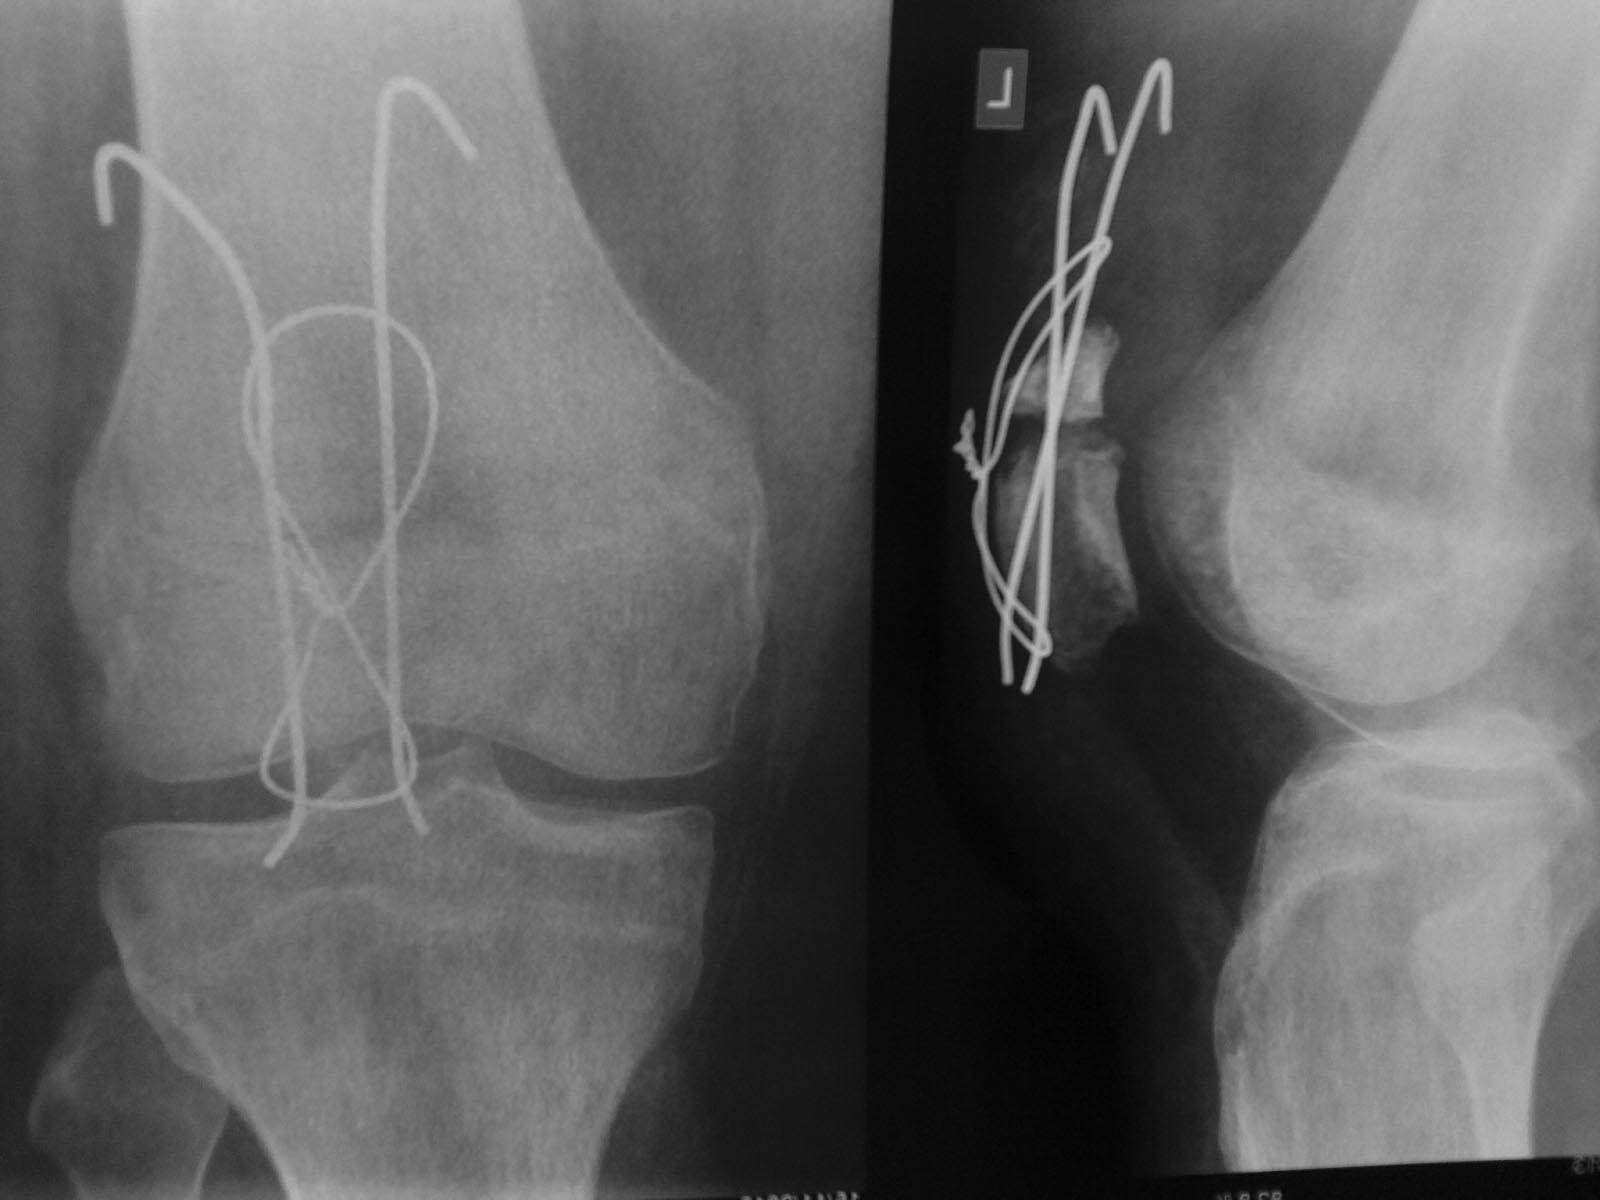

Прошу прощения у коллег, так как писал "на скорую руку" с чужого компьютера

Выкдадываю новые снимки

Хочу отметить, что перелом на уровне верхнего (проксимального) полюса (первое фото просто вводит в заблуждение)

Концы спиц при первой операции были оставлены достаточно длинными с проксимальной стороны, собственно при втором МОСе там образовался такой "конгломерат" соединительной ткани, что разрушать его для того, чтобы откусить ближе к кости не было желания, хотя про реабилитацию подумал

Контрактура есть разгибательная, но после снятия ортеза (до синтеза еще) под наркозом смог согнуть колено свободно до 90 градусов

В МОСе не очень уверен (при пробе сгибания интраопериционно лопала проволока трижды), поэтому лечу в ортезе

Вот сколько лечить, чтобы не "залечить до контрактуры" и не нарушить МОС, не знаю

По-поводу снимков - первый остеосинтез выглядит посимпатичней. Непонятно почему через 3 месяца удален металл, считаю это серьезной тактической ошибкой, надо не ранее, чем через год, ибо нагрузки здесь весьма большие. При повторной операции адаптация отломков похуже - есть ступенька. При первичном остеосинтезе и отсутствии контрактуры возможна иммобилизация до 5-6 недель. При повторном остеосинтезе и наличии контрактуры разрабатывать надо почти сразу. Если проволока подведет надо быть готовым к повторной операции и выбрать фиксацию понадежней.

На рентгенограммах открываются изумительные виды из Вашего окна, но сустав практически не виден. Всё-таки следует рассматривать сустав целиком, а не только крупное изображение надколенника.

скорее всего при ранней разработке ничего не получиться - отломки наверняка разойдуться(на проксимальном отломке петля не лежит на кости,и вот на такое же растояние и разойдуться)Но учитывая мнениие большинства вы начните разработку и через недельку сделайте контроль.Потом во всех бедах обвините тактично жирного больного(ну как кролик винипуха).Вот тут-то можно вспомнить Гавриила Абрамовича Илизарова и его методику закрытого чрезкостного остеосинтеза.Удачи!

По поводу проволоки - так и не смог ее положить ближе к кости (с проксимальной стороны) - поэтому и боюсь рекомендовать раннюю реабилитацию, так как отломки могут разойтись. С другой стороны проволоку ложил максимально близко к кости, но скальпель не позволил отделить ткани возле проксимального отломка (настолько они были склерозированы, что посчитал их непосредственно костью - по мне произошло это из-за изменения тканей ввиду длинных концов спиц, оставленных при первой операции)

Именно поэтому технически оставлены не до конца обкуманными спицы и не проведена ближе к кости проволока

Но в ортезе собираюсь подержать не менее месяца (чтобы хоть что-то сраслось)